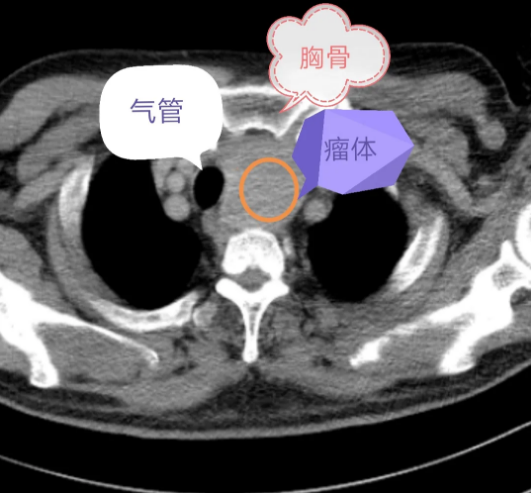

患者王先生1月前查体时发现颈部肿物,并出现吞咽不畅,夜间偶有呼吸困难等症状。就诊于多家医院,诊断为甲状腺肿物,因肿物位置特殊,位于胸骨后,并且肿物体积较大,约8×5×3cm大小,与周围组织界限欠清楚,遂建议劈开胸骨给予手术治疗。患者本人及家属觉得手术创伤太大,一直犹豫不决。

但随着瘤体的增大,患者气管、食管的压迫症状已逐渐明显,考虑如果破裂病情将加重等情况,治疗已刻不容缓。患者辗转多家医院后入住淄博市第四人民医院,外科二组协同放射科、超声科会诊后考虑患者肿物可能为甲状腺囊肿囊内出血所致,但也不排除甲状腺恶性疾病。如果单纯给予穿刺硬化、穿刺抽吸可能会对下一步手术造成困难。遂考虑给予手术治疗,并请省科学院陶阳主任医师参与会诊,指出可先行甲状腺切口,探查后缩小肿物体积的方式取出肿物。术中所见如术前推测,为巧克力状内容物,但肿物位置较深,可探及锁骨下动脉,在有效分离、保护血管及喉返等神经后,顺利完成手术。